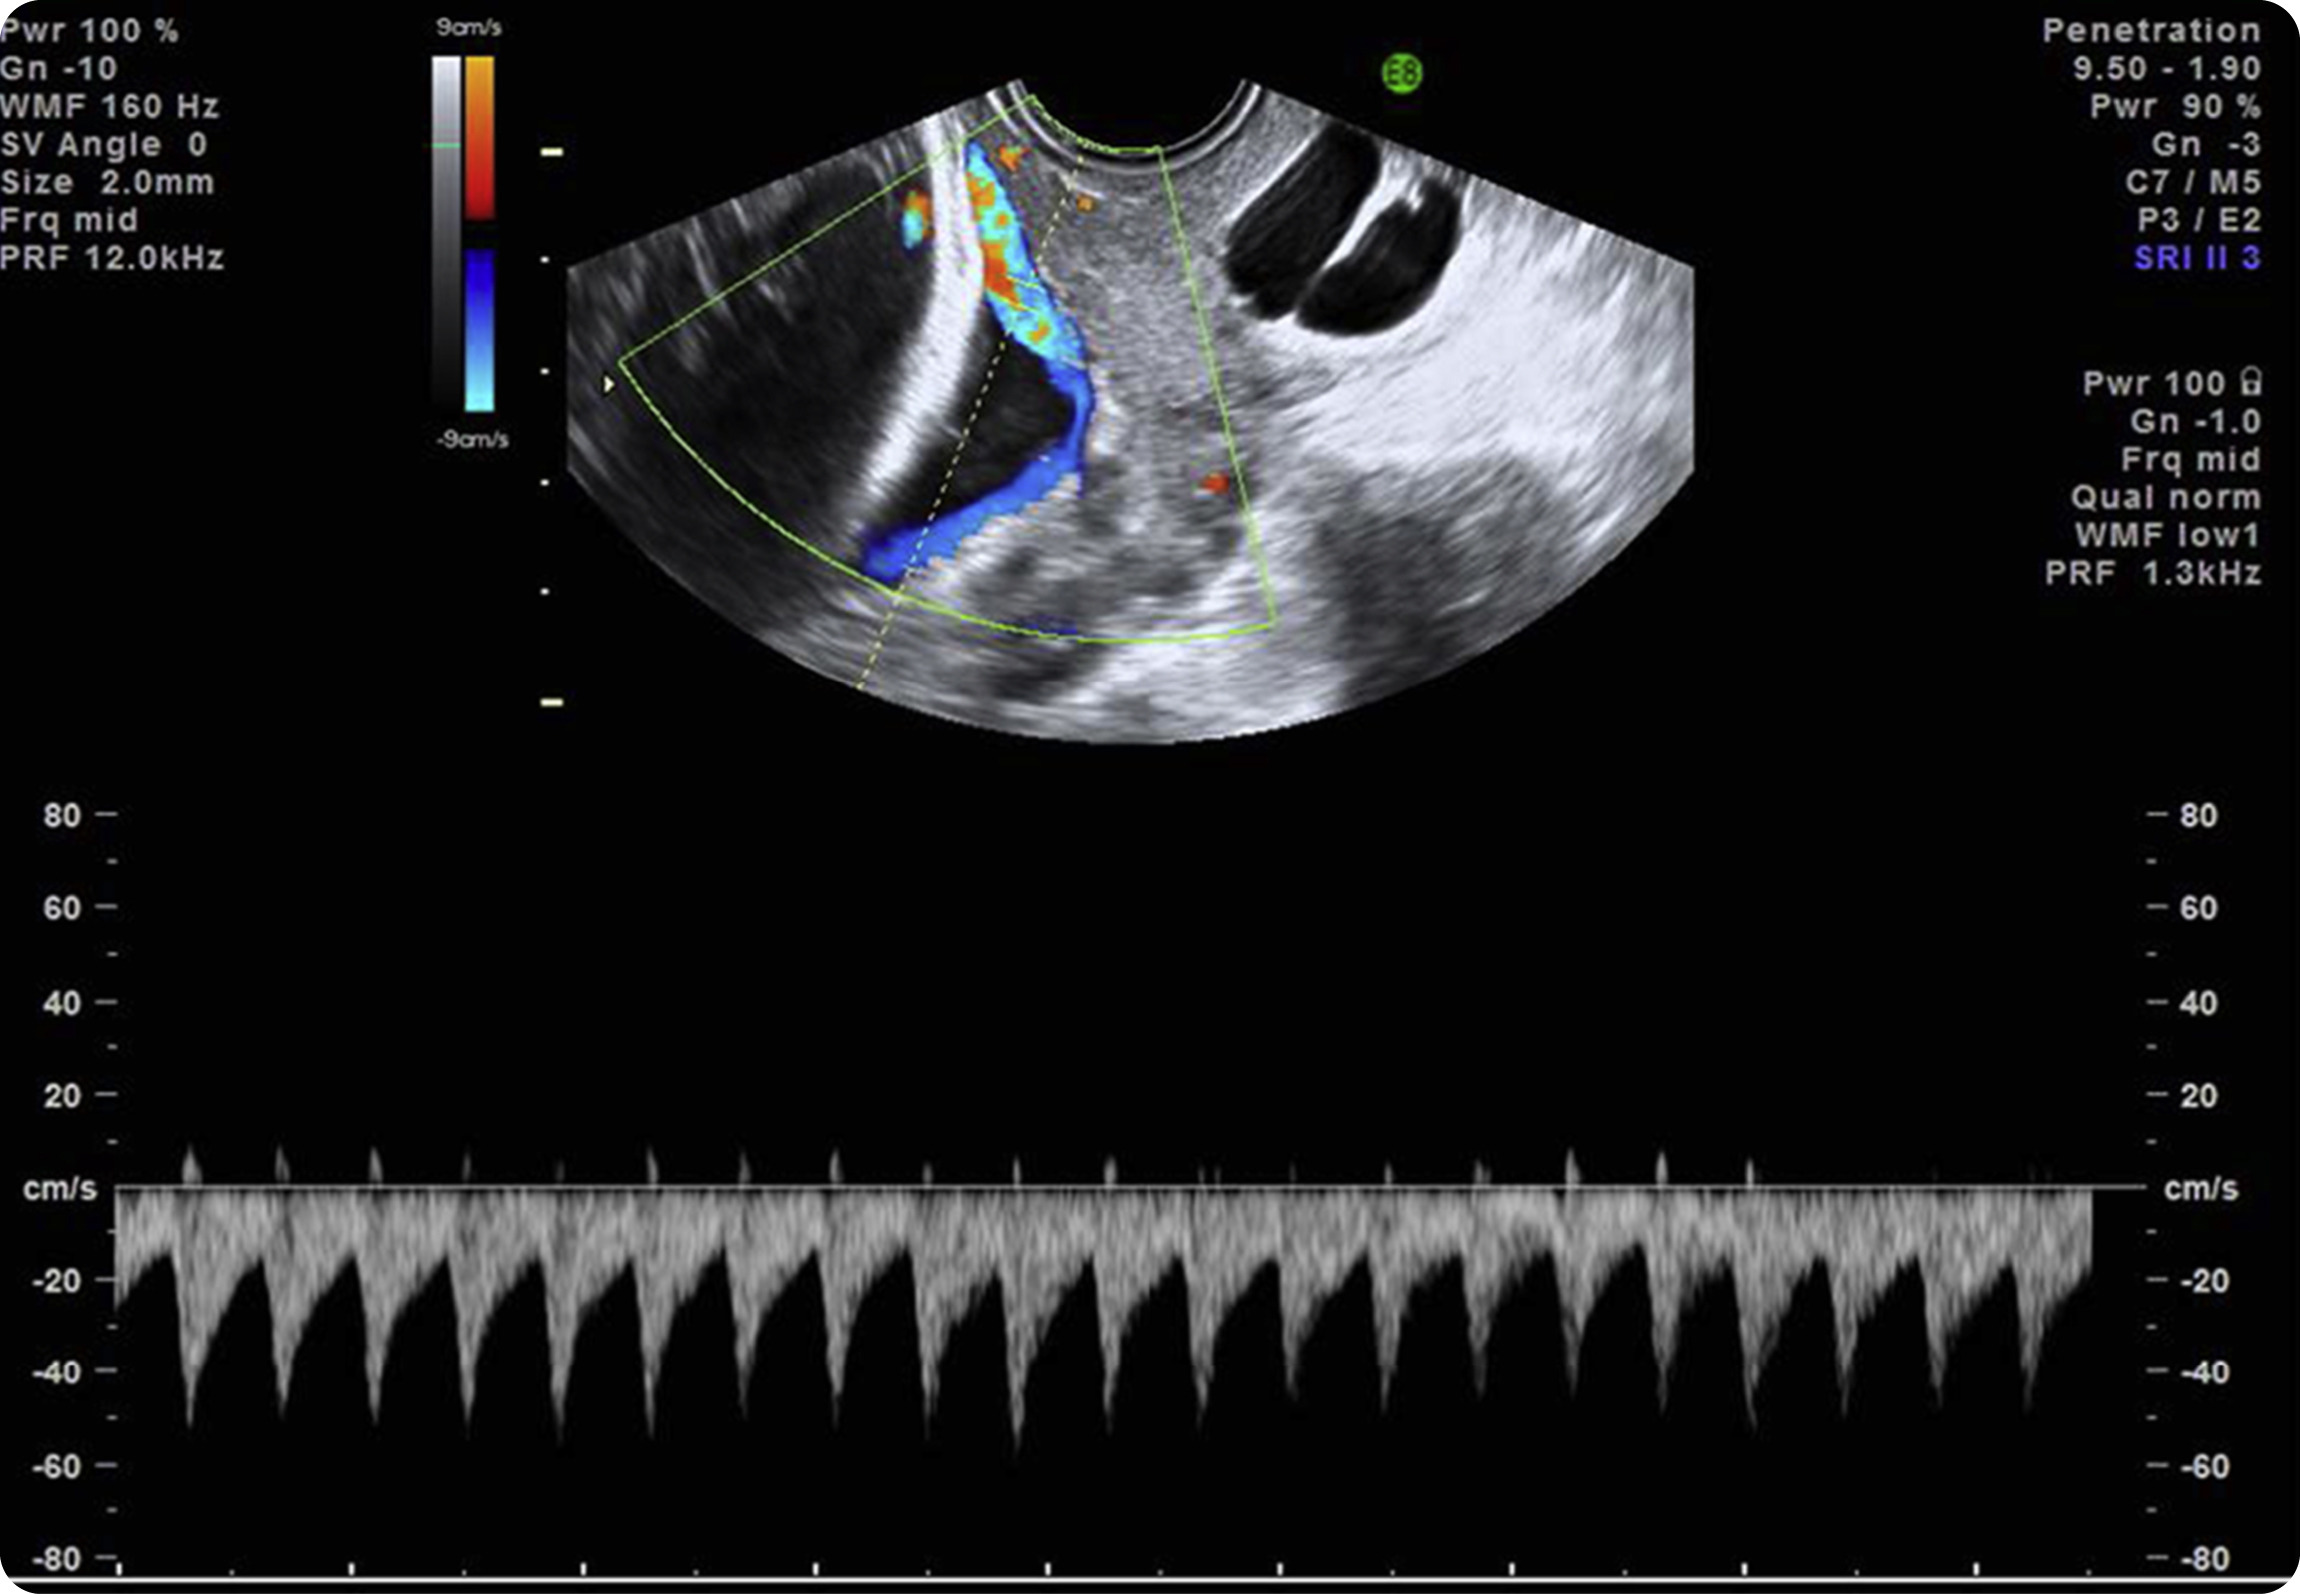

Figure 3. Transvaginal ultrasound scan with color Doppler image and pulsed wave Doppler image shows fetal heart rate

Anna Euser, MD, PhDPulsed wave Doppler of the vessel over the cervical os depicts a fetal heart rate, confirming a diagnosis of vasa previa.

Source: SMFM. Diagnosis and management of vasa previa. Am J Obstet Gynecol 2015.

Vasa previas, best diagnosed by endovaginal ultrasound, carry significant fetal morbidity/mortality risk. This risk is dramatically reduced when diagnosed prenatally, as compared to postnatally.

Most vasa previas (60%) at term occur in the context of a resolved previa or low-lying placenta. As such, endovaginal ultrasound with color Doppler is recommended for ALL patients presenting for follow-up of placental location (prior placenta previa or low-lying placenta) even if abdominal ultrasound suggests that the placenta is >2cm from the cervix.